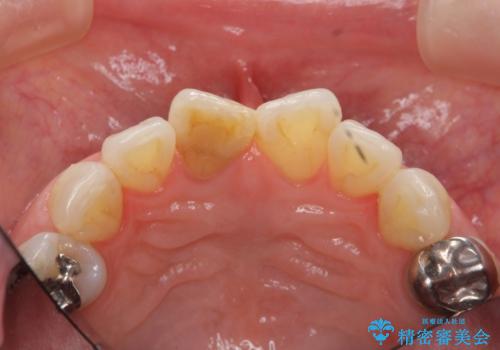

前歯の変色 セラミック審美補綴

- 前歯の変色の改善を希望され来院されました.

以前に神経が死に、根管治療を行った歯の変色が認められたためセラミックによる審美補綴治療を計画します。

神経の死んでいる歯について

神経治療を行い補綴(かぶせもの)治療を行わないと、変色が目立ち審美障害を起こすことがあります。

このような場合、セラミックによる審美改善が治療の一案として提案されます。